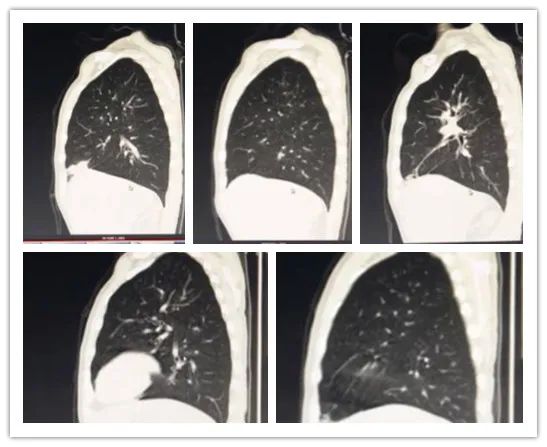

李某,男,26岁,白血病病史,行胸部CT检查,排除肺部浸润情况。

影像所见:

双肺纹理增粗、模糊,双肺见弥漫性斑点状阴影;中肺野见小团片状影,边界尚清,大小约2.1×3.3cm,周围见小斑片模糊影及条索影,邻近胸膜受牵拉,粘膜增厚。

矢状位图像

矢状位见双肺纹理增粗、模糊,双肺见弥漫性斑点状阴影。